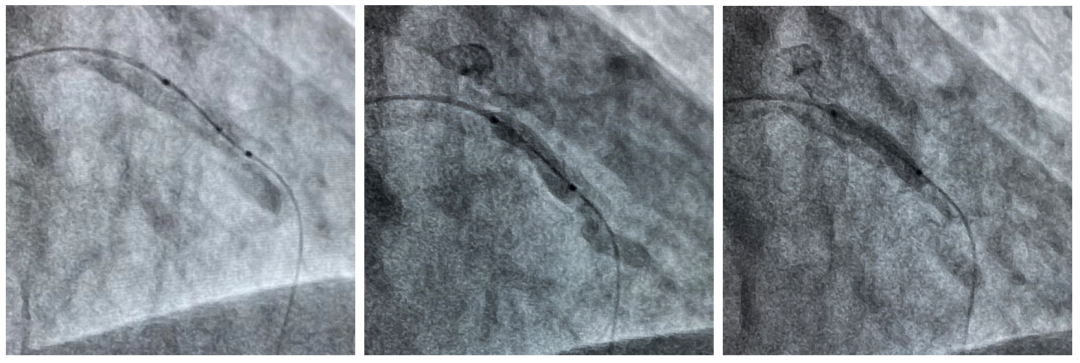

导管支持下通过Shockwave球囊(左)

初始Shockwave不能完全膨胀(中)

冲击治疗后Shockwave球囊完全膨胀(右)

延长导管支持下,3.0mmx12mm Shockwave冲击波球囊精准定位于前降支近段钙化最重处,先后触发60次脉冲冲击波(6个周期),实施钙化斑块碎裂术,对治疗段进行低压球囊扩张成形,随后通过OCT及冠脉造影融合技术证实,部分钙化病变得到松解,但中段成角病变处OCT提示仍有严重偏心钙化斑块,再次进行了20次脉冲冲击波(2个周期)治疗后,随着shockwave球囊能量的逐步释放,再次复查OCT显示原钙化环断裂,深层钙化碎裂。经过充分的冲击波球囊预处理,顺利完成进一步介入治疗。用时约40分钟,在患者无明显不适的情况下顺利完成介入治疗。术后患者顺利转入病房,并计划于近日出院。